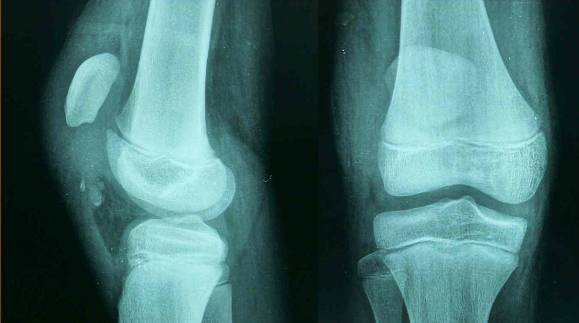

交叉韧带损伤

1、股内侧肌。2、股四头肌肌腱。3、髌骨。4、髌韧带。5、前交叉韧带。6、胫骨。7、腓肠肌内侧头。8、后交叉韧带。